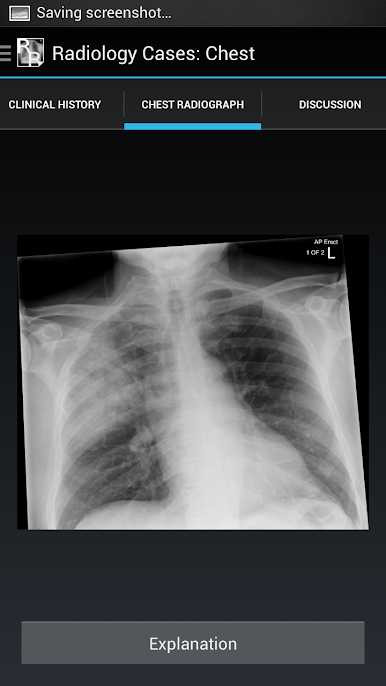

It consists of 26 cases, each with a brief history and a chest x-ray. The user should try to interpret each chest x-ray before revealing the explanations at the bottom of each page.

The aim is to gain an understanding of the basic principles of chest x-ray interpretation and specific radiographic features of common diseases. The diseases encountered are discussed along the way and many of the cases have a scrollable

CT to help with understanding the chest x-ray appearances.